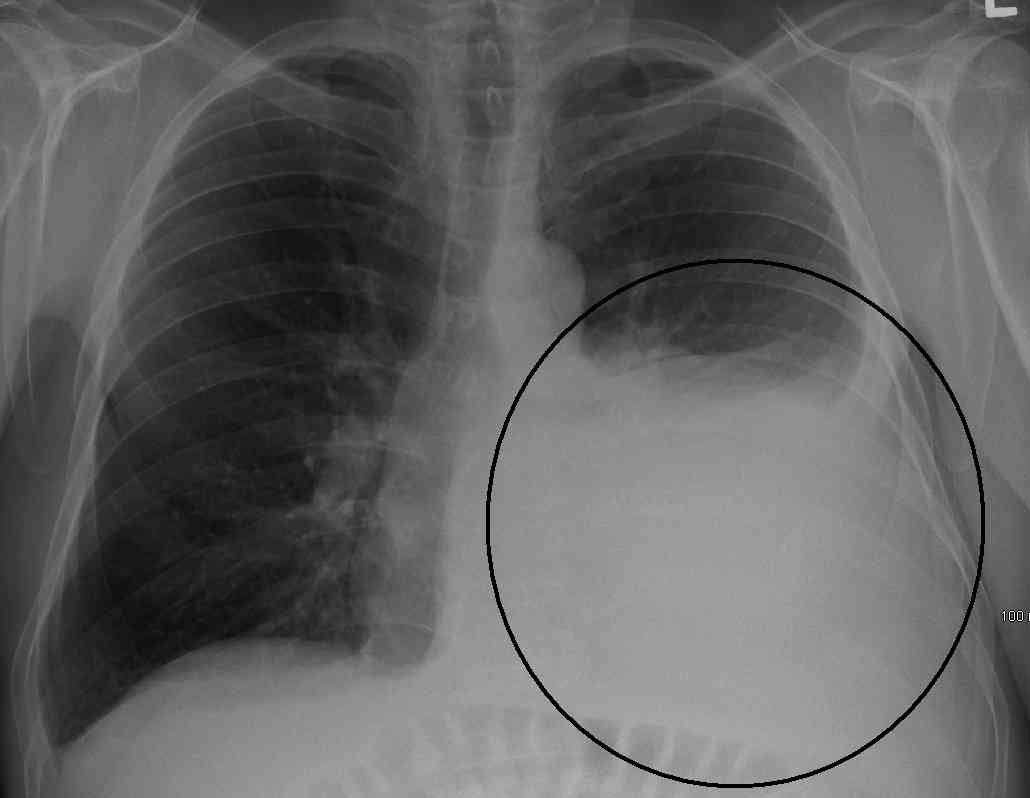

Οι γιατροί χρησιμοποιούν τον όρο πνευμονικό οίδημα για να περιγράψουν τη διαδικασία συσσώρευσης υγρού στον πνεύμονα. Το πνευμονικό οίδημα οφείλεται στην πλειονότητα των περιπτώσεων σε καρδιαγγειακή επιπλοκή (καρδιογενές ή καρδιογενητικό πνευμονικό οίδημα).

Το καρδιογενές πνευμονικό οίδημα είναι αποτέλεσμα της αυξημένης πίεσης και καταπόνησης της καρδιάς.